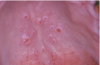

What is this radiographic & clinical findings?

Periapical cyst

shows inflammation at site

abscess developed fistula tract thru

soft tissue. Pt will have pain until

pressure is released